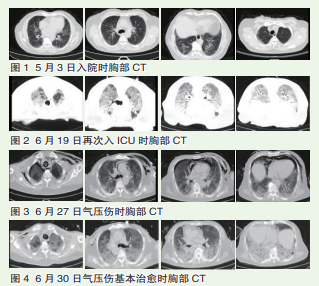

辅助检查     血气分析: 动脉血氧分压 :86 mmHg; 动脉血氧饱和度 :97.7%。 新冠病毒核酸阳性。5 月 3 日胸部 CT 显示,两肺间 质性炎症,左肺上磨玻璃 影,炎性病变可能,两侧 少量胸水(图 1)。

治疗经过    患者入院后 给氧,给予抗炎、抗病毒、 抗凝等治疗,效果不佳, 后患者血氧饱和度下降至 70% 左右,气管插管后转 入监护室,给予抗炎、抗 感染治疗,5 月 12 拔除气 管插管,后转入普通病房 治疗。6 月 18 患者血氧饱 和度下降至 75% 左右,转 入监护室。6 月 19 日胸部 CT 显示患者,两肺弥漫 性渗出炎症,两侧微量胸 水(图 2)。给予患者气 管插管有创机械通气(间 断俯卧位)。

6 月 27 日患者出现呼 吸频率增快,气促明显, 查体皮下触及握雪感,床 旁超声检查气影伪像,心 脏无法显像。胸部 CT 显 示,患者两肺弥漫性渗出 炎症较前明显吸收,右侧 少量气胸,纵隔气肿,胸 壁皮下气肿(图 3)。考 虑右侧胸腔少量气胸,胸 腔穿刺风险巨大,未行胸 腔穿刺置管闭适引流,给 予患者镇静镇痛肌松,继 续机械通气(间断俯卧位), 容量控制模式,潮气量为 5 ml/kg( 理想体重), PEEP 5cmH2O。6 月 30 日 胸部 CT 显示,患者肺弥 漫性渗出炎症较增多,右 侧少量气胸及纵隔气肿吸 收,左侧胸壁少量皮下气 肿(图 4)。